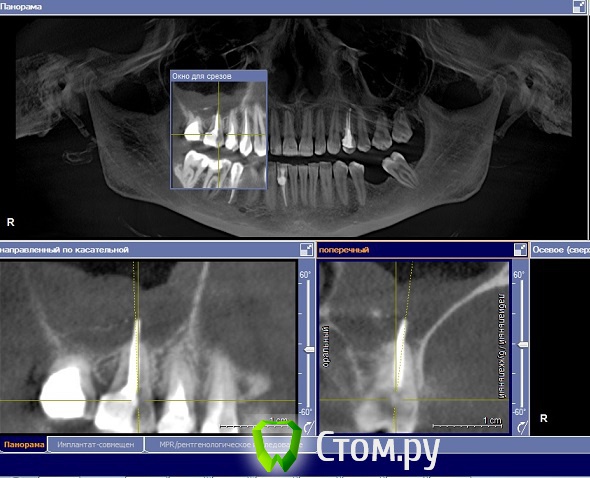

Yniversal Опубликовано 26 ноября, 2013 Поделиться Опубликовано 26 ноября, 2013 Здраствуйте уважаемые коллеги!Хотелось бы узнать ваше мнения по поводу тактики ведения данных пациентов , возможности проведения синус-лифтинга и имплантации.Спасибо 1. 15-продольная фрактура коронки и верхней трети корня.Изменения слизистой пазухи.Выведение ПМ за верхушку.Клиники синусита нет.16 перкуссия "-"2. После кт исследования проведены удаления 25 26 27. Клиника синусита не выражена.Пациент жалоб не предьявляет.3.16 удален несколько лет назад.Клиники со стороны пазухи не выявлено Ссылка на комментарий